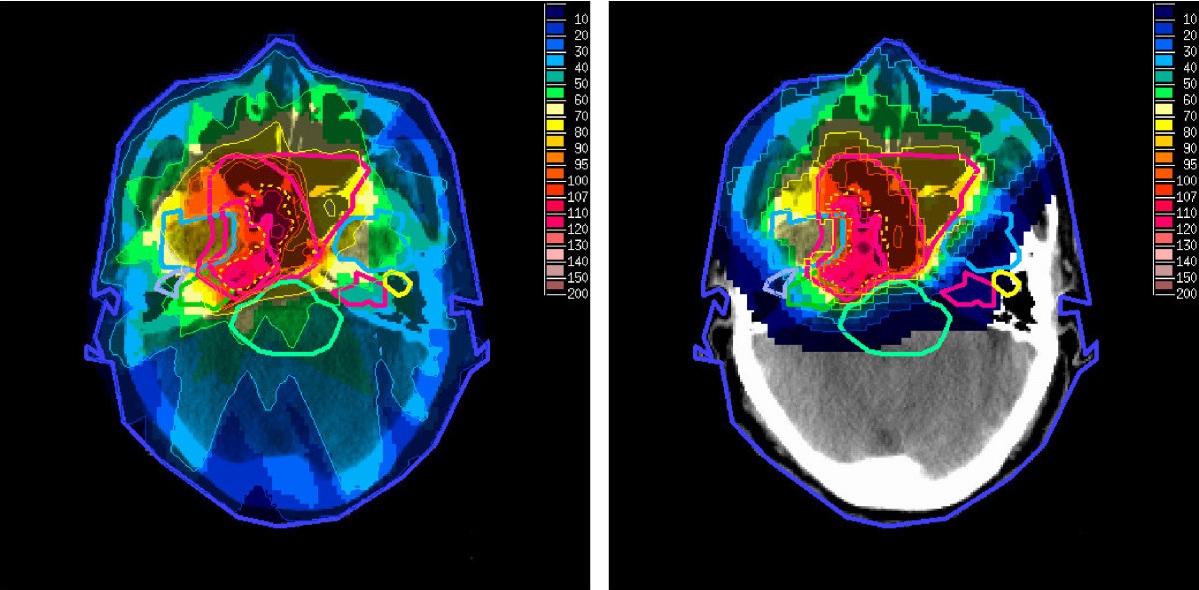

Når vi skal bestråle en kreftsvulst og hindre at den formerer seg videre, er det viktig at vi ikke skader friske organer med strålingen. Det er nødvendig å vite hva vi treffer og om andre organer «ligger i veien» for svulsten. Når vi lager en plan for hvordan vi skal levere strålingen trenger vi et bilde av hvordan pasienten ser ut inni.

Planlegging av strålebehandlingen

I forkant av strålebehandling (enten med fotoner eller protoner) trenger vi detaljert informasjon om området vi skal behandle. I dag bruker vi en CT-skanner, som gir et tredimensjonalt røntgenbilde. CT-skanneren sier hvordan røntgenstråler passerer gjennom pasienten, så de verdiene må vi oversette til hvordan protoner oppfører seg. Oversettelsen gir en usikkerhet på opptil 1 cm på hvor strålingsdosen leveres, og den må vi ta hensyn til når vi planlegger behandlingen.

Leger og fysikere samarbeider så om å lage en detaljert behandlingsplan hvor det bestemmes hvor og hvordan vi skal bestråle pasienten. Vi bruker alltid et utvidet behandlingsområde, slik at vi er sikker på at målvolumet får nødvendig strålingsdose. Vi bestemmer også hvilke organer som ikke bør bestråles. Usikkerhetene fører til at friske organer mottar unødvendig strålingsdose, og vi får ikke utnyttet teknologien slik vi ønsker.